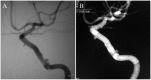

Case description: We report on a 63-year-old male who had a large internal carotid artery cavernous segment aneurysm. Treatment with PED resulted in complete occlusion of the aneurysm. However, follow-up angiography at four years revealed recurrence of the aneurysm due to disconnection of the two PEDs placed in telescoping fashion.